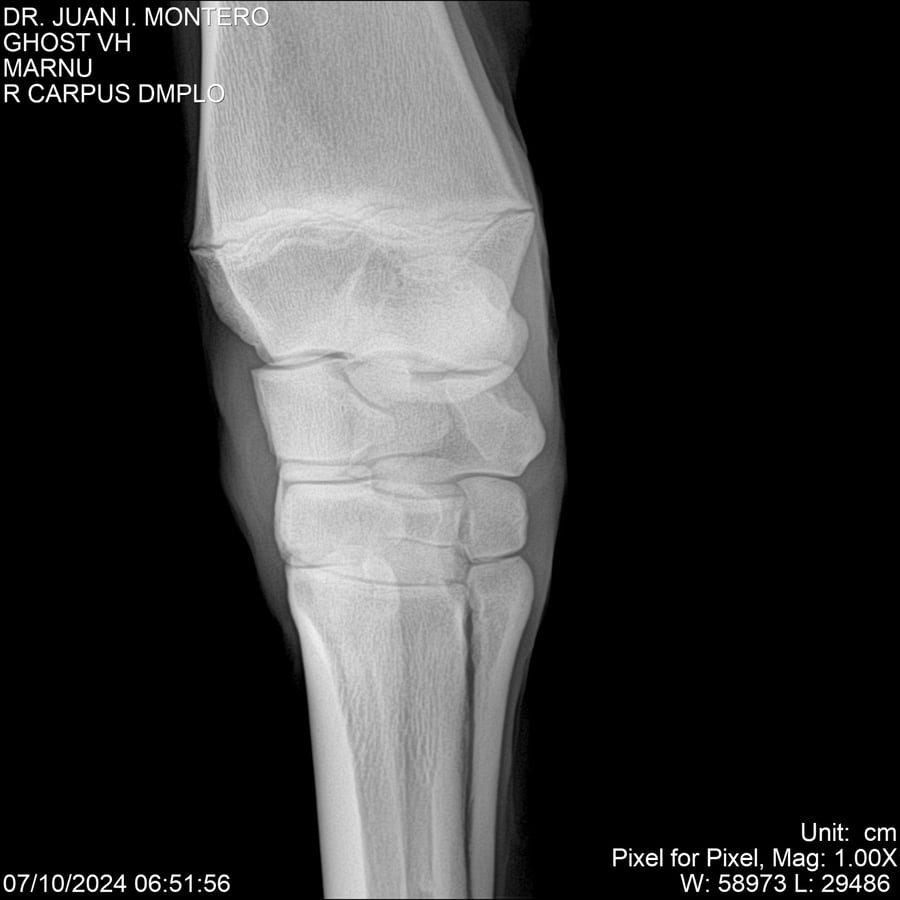

LOTE 15, GHOST VH 🔥 🔥 🔥 Lote Anterior Volver al remate Lote Siguiente Ficha Contacto Montevideo - Ficha del Lote Identificador: #282525 Categoría: Yeguarizos Montevideo - 69 Visualizaciones ClicData Contacto Empresa: Abelenda N. R., Walter Hugo Nombre*: Teléfono* : E-mail* : Mensaje Enviar Registrese gratis Este contenido Exclusivo está disponible sólo para usuarios registrados Ingresar